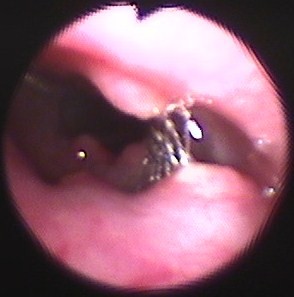

合併症:シリコンステントで喀痰増加、BAL中細胞数増加(3665/μl)、Wallstent留置で前方気管虚脱、ステント前端および内部に肉芽形成(図7)→ヒトの報告に基づき33、APC焼灼+MMC塗布;3ヶ月間は抑制可(図8-10)。現在、follow中(1010日間)。

図7 症例1の第475病日。気管支鏡検査所見。ステント前端および内部に反応性肉芽形成。

図8 症例1の第538病日。2週間ごとにマイトマイシンCを肉芽部分に塗布し、肉芽消失。

図9 症例1の第1010病日。アルゴンプラズマ凝固(APC)およびマイトマイシンC(MMC)塗布したが、4ヵ月たつと肉芽再発。

図10 図9と同日、内視鏡で診断後、ただちにAPCおよびMMC塗布し、ただちに気道開存を得た。